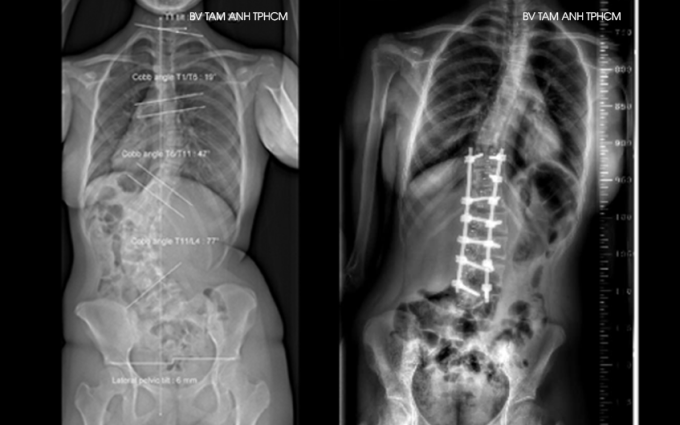

Kết quả chụp X-quang tại Bệnh viện Đa khoa Tâm Anh TP HCM gần đây cho thấy cột sống của An có hai vùng biến dạng, vùng ngực vẹo sang phải 47 độ và vùng thắt lưng vẹo sang trái 77 độ, thắt lưng xoay nhiều. Người bệnh bị lệch vai, lưng biến dạng đến mức có thể nhận ra bằng mắt thường và đau nhiều khi ngồi.

Phim chụp X-quang cột sống của An trước (trái) và sau phẫu thuật. Ảnh: Bệnh viện Đa khoa Tâm Anh